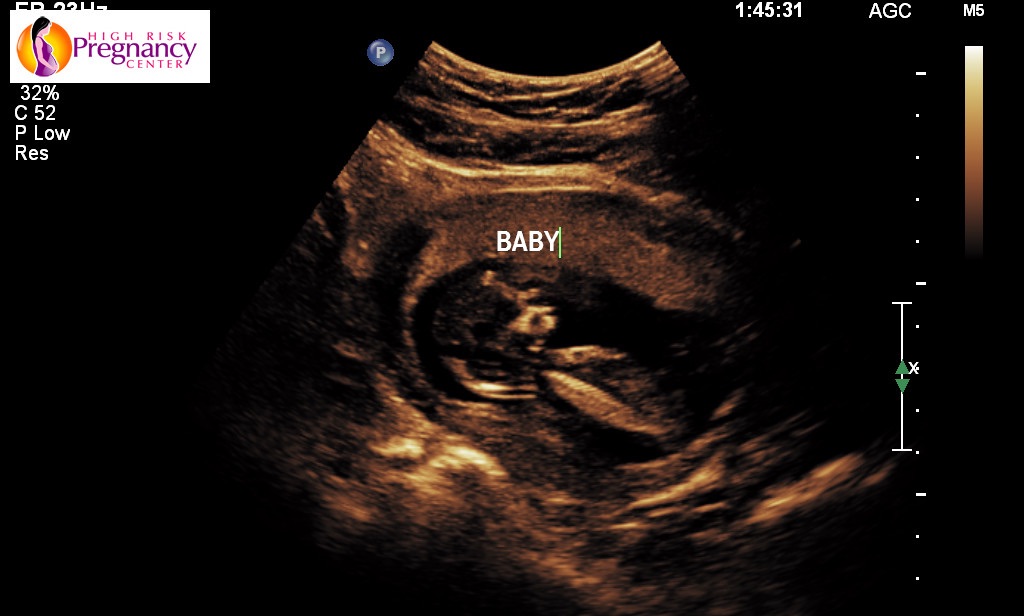

12 weeks, 1 day. First ultrasound that looked like a real baby! So exciting!

image.jpg